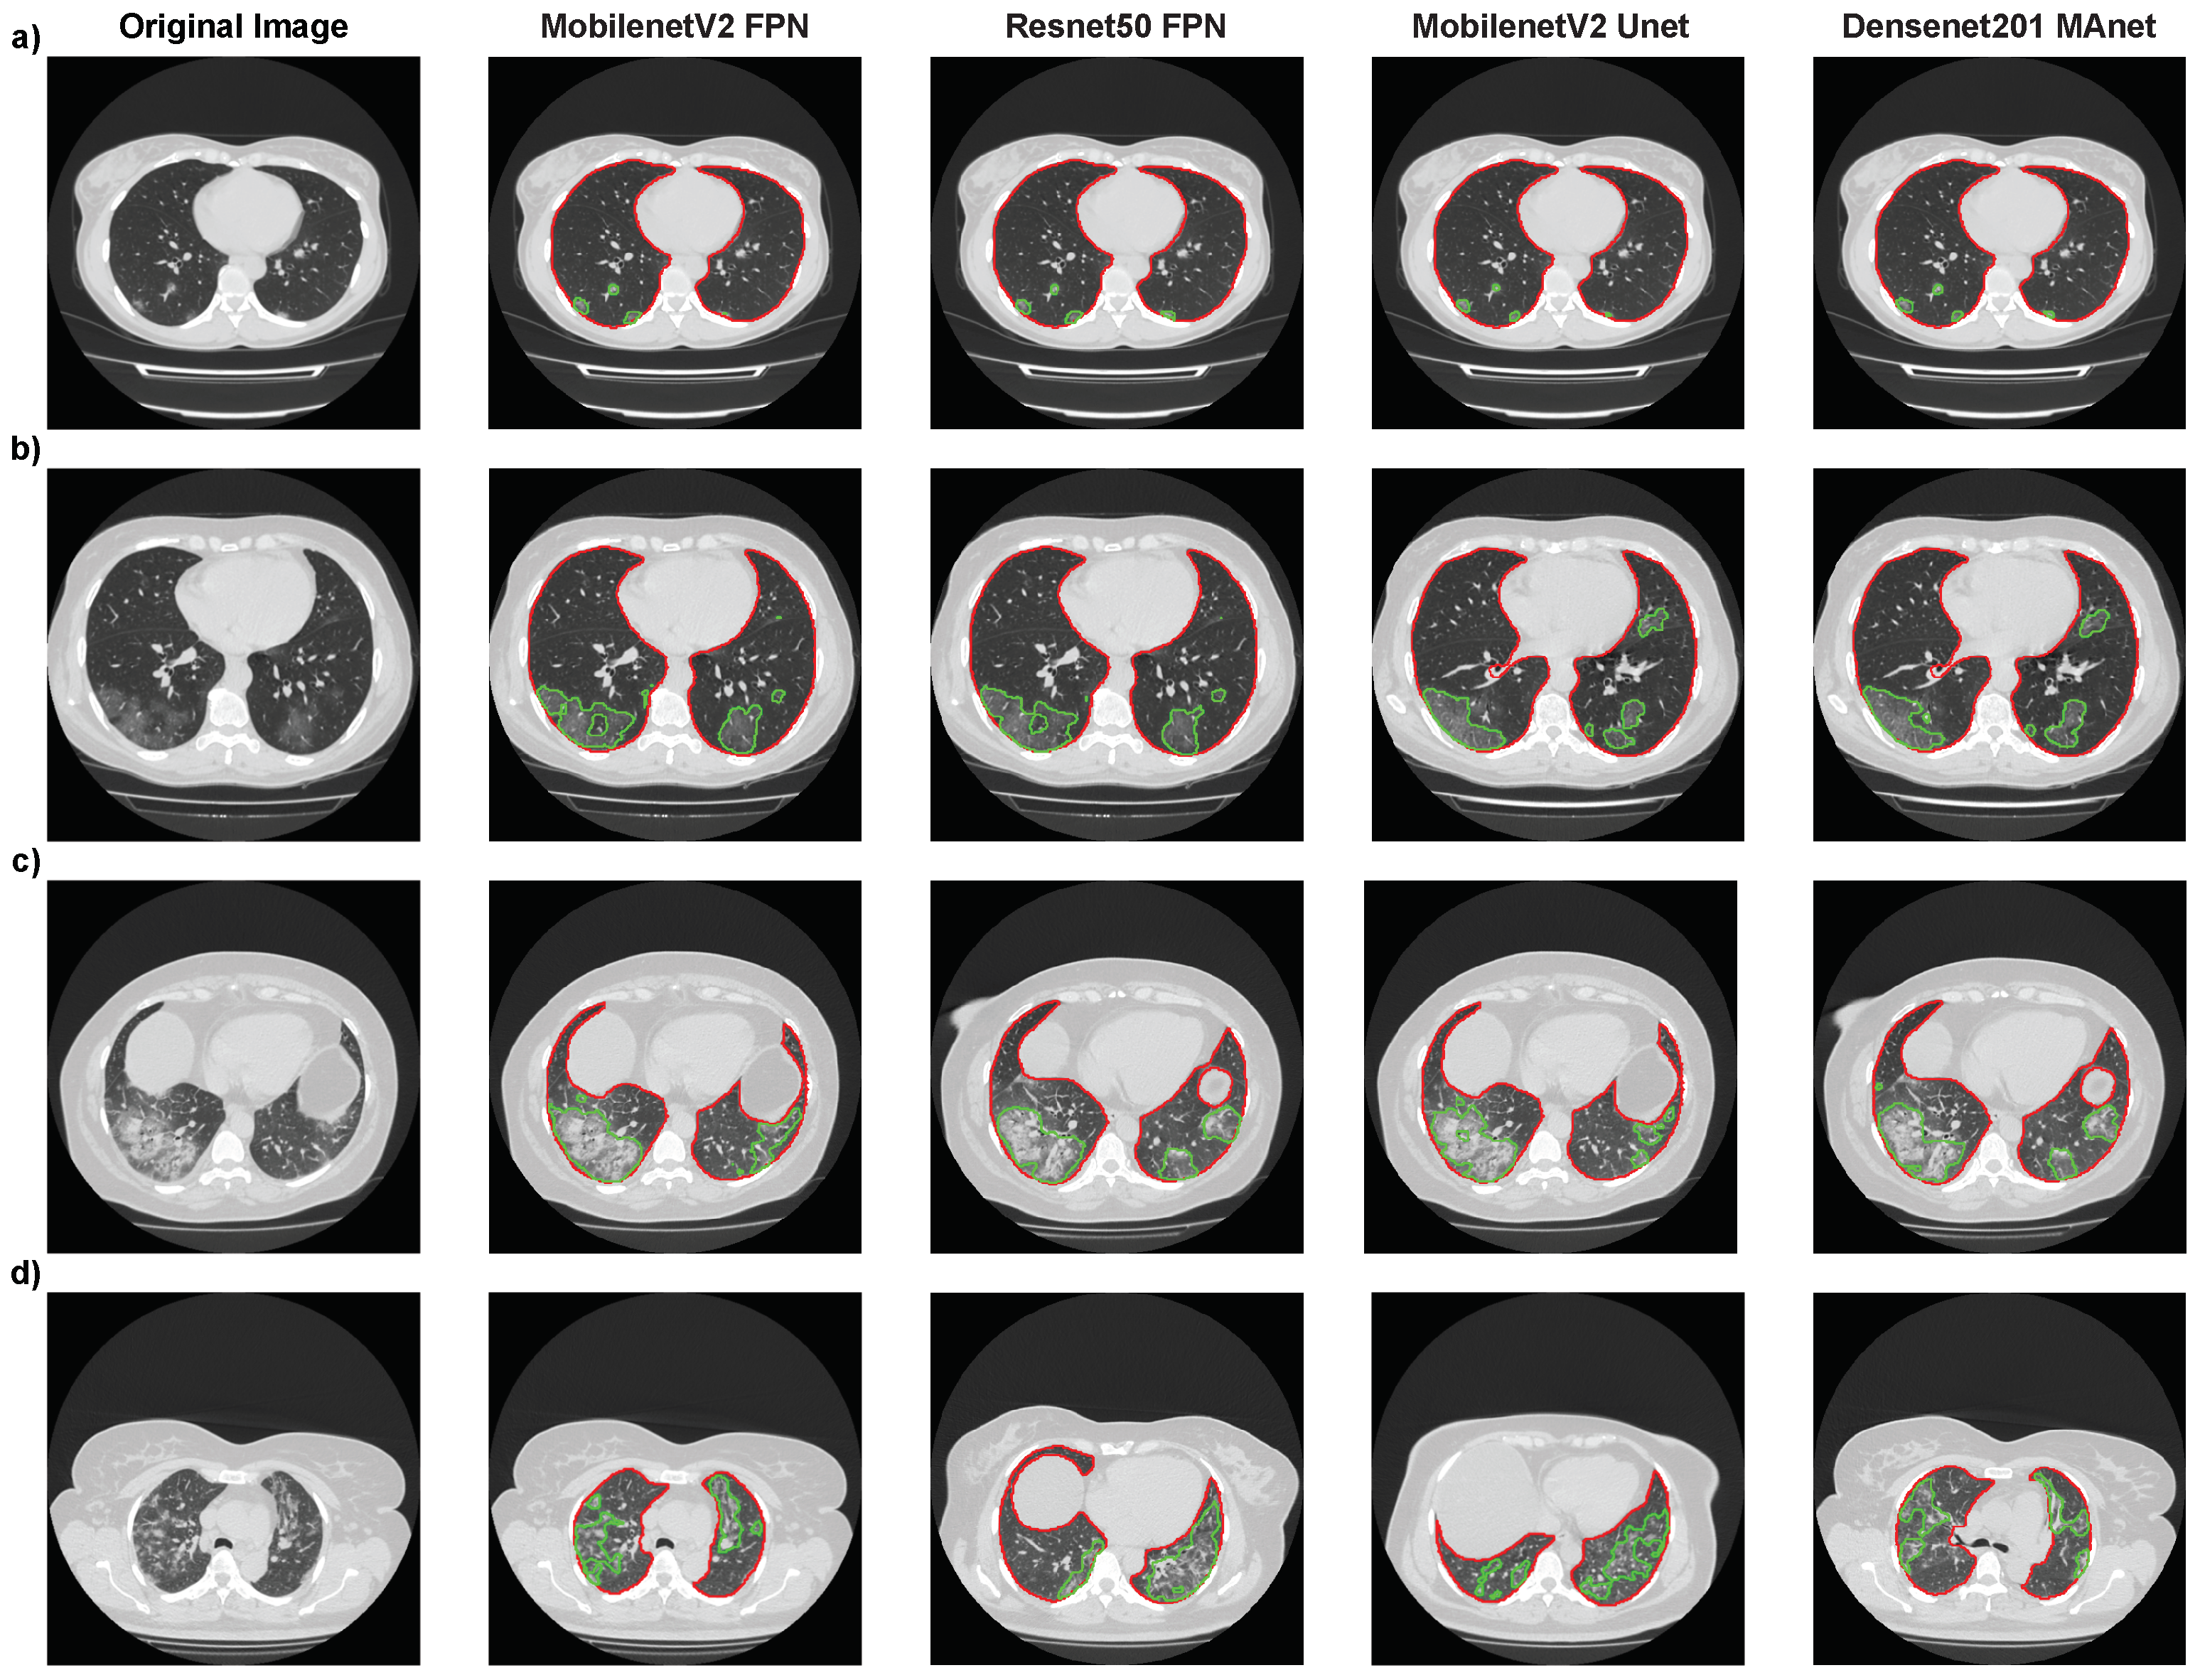

Again, Mobilenet Unet obtained the highest results, with accuracy of 75.05%, F1-score of 73.26%, precision of 72.67%, and recall of 75.05%. Even if the metrics were not as high as for binary classification (“without lesion” or “with lesion”), Figure 10 shows, for four architectures (Resnet50 FPN, Mobilenet FPN, Mobilenet Unet, and Densenet MAnet), that our pipeline correctly segmented most lesions presented on the CT scans. The lower metrics obtained might have been due to the qualitative analysis made when labeling MosMedData, which we could not replicate with quantitative values.

We present the images where each model found the most extensive lesion area for that specific exam. The experiment found that all architectures could locate lesions in the same lung areas, indicating consistent performance. However, some architectures were unable to accurately identify certain lesion areas. Specifically, the MobilenetV2 FPN architecture failed to locate a small lesion in the right lung in the presented image (Figure 10a), while the other three architectures correctly identified it. These findings suggest that while all architectures performed similarly overall, there were still differences in their ability to accurately identify certain lesion areas, highlighting the importance of selecting the most suitable architecture for a specific task. These difficulties in detecting certain lesion areas could have worsened the results presented in the confusion matrices in Table 13.

Figure 10. Segmentation results of Resnet50 FPN, Mobilenet FPN, Mobilenet Unet, and Densenet MAnet on MosMedData. Lung segmentation is represented by red contours, and lesion segmentation is represented by green contours. (a) Image from an exam of class 1. (b) Image from an exam of class 2. (c) Image from an exam of class 3. (d) Image from an exam of class 4.